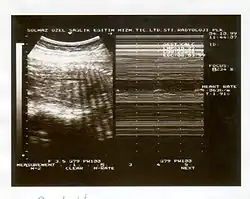

Il se réalise au cours d'une échographie, qui recherchera 5 critères (durant 30 minutes), un critère présent comptant pour 2 points (et 0 s'il est absent) :

- réactivité du rythme cardiaque fœtal,